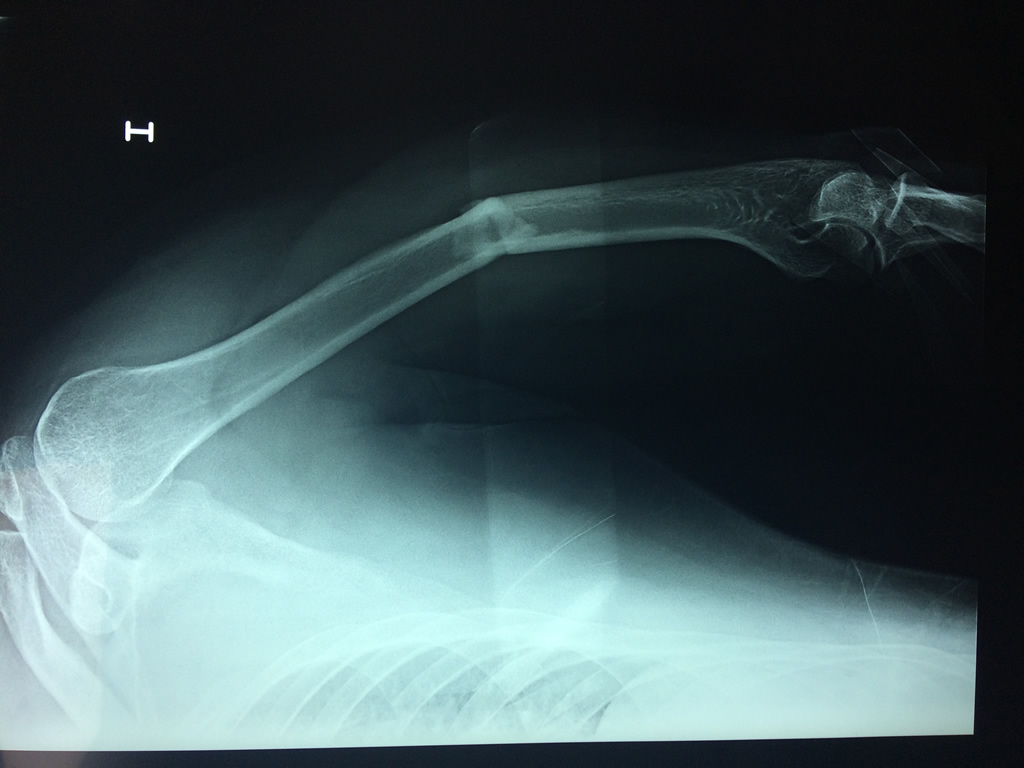

Cirugías de Calcaneo - Húmero

El Húmero (en latín, humerus) es el hueso más largo de las extremidades superiores en el ser humano. Forma parte del esqueleto apendicular superior y está ubicado en la región del brazo. ... El extremo proximal del húmero tiene la cabeza, cuellos quirúrgico y anatómico y tubérculos mayor y menor.